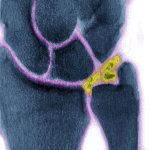

Vôi hóa sụn khớp (Chondrocalcinosis) còn gọi là vôi hóa sụn khớp lan tỏa hay giả goutte, nằm trong nhóm bệnh viêm khớp vi tinh thể: gồm bệnh gout, bệnh vôi hóa sụn khớp và viêm khớp sau khi tiêm Steroid nội khớp. Vôi hóa sụn khớp được đặc trưng bởi hiện tượng lắng đọng calci ở mô sụn và mô xơ sụn…